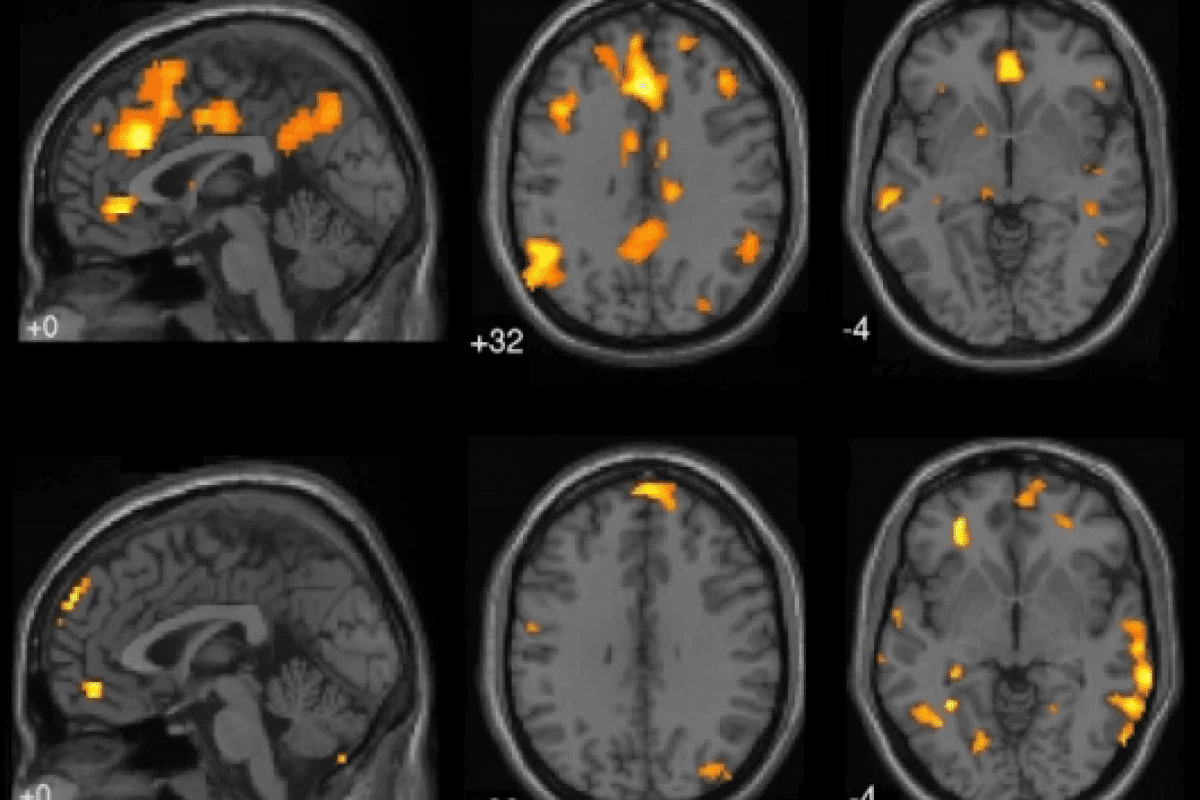

Neuroimaging Techniques

Neuroimaging is vital for spotting brain metastases. Magnetic Resonance Imaging (MRI) is top for this job. It shows brain details clearly and finds metastases well.

Computed Tomography (CT) scans are also used. They’re quick and help in emergencies. Though not as good as MRI for small spots, they’re useful for bigger ones and related issues.